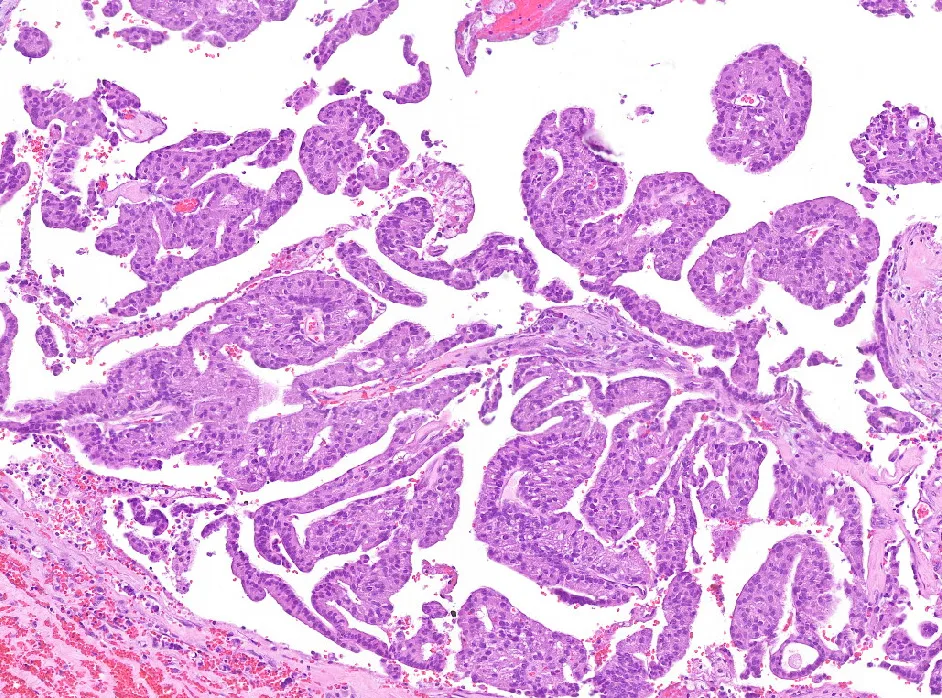

2-H&E2

Diagnóstico: Adenocarcinoma mucinoso, anteriormente denominado cistoadenocarcinoma papilar, de grado intermedio de localización amigdalar.

- Histológicamente se caracterizan por áreas quísticas y sólidas con múltiples proyecciones papilares luminales que tienen un núcleo fibrovascular y están revestidas por células epiteliales cúbicas, columnares o secretoras de moco. Inmunohistoquímicamente es CK7, CEA y EMA positivo, siendo negativo para otros marcadores de glándula salival. (PMID: 35252049)